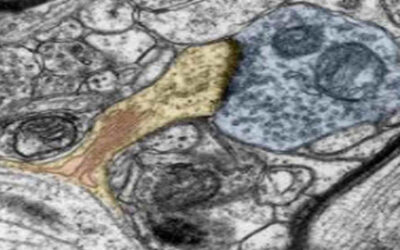

Conocer mejor la DMAE Por qué los investigadores consideran que la DMAE es un espectro de enfermedades y no una sola. Un artículo de revisión recientemente publicado sobre la degeneración macular asociada a la edad (DMAE) presenta un debate exhaustivo sobre los...